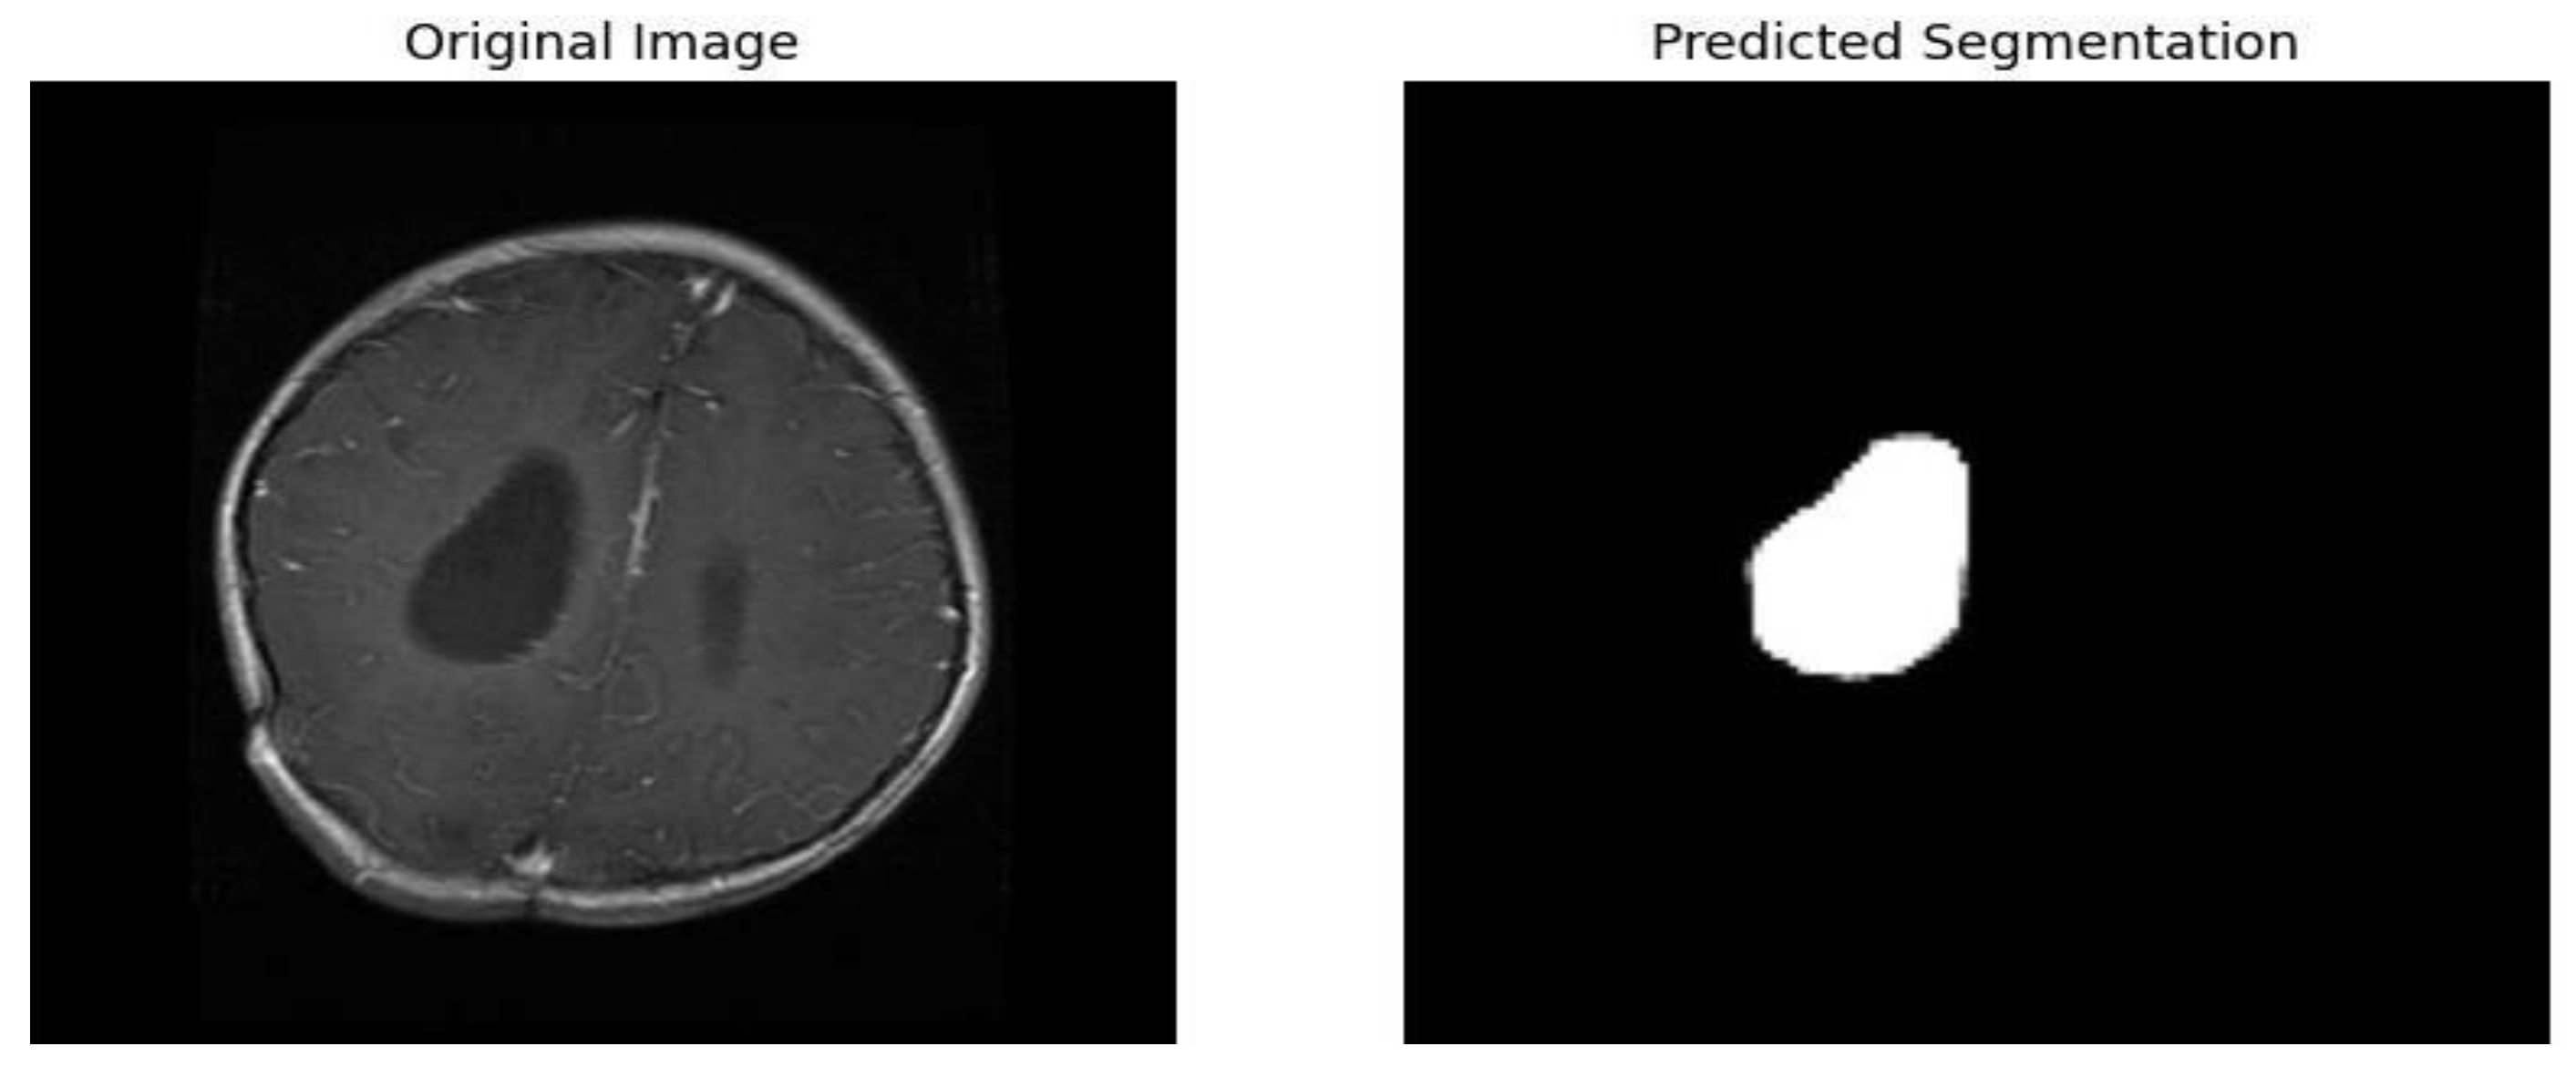

3.5.2. Segmentation

3.5.2.3. Model Architecture

- Use 3x3 convolutional layers with padding to preserve spatial dimensions.

- Employ ReLU activation functions after each convolution.

- Use max-pooling layers with a pool size of 2x2 for down-sampling.

- Use transposed convolutions for up-sampling in the decoder part.

- Apply dropout layers where necessary to prevent over-fitting.

3.5.2.4. Training Procedure

- We split the data set into training, and test sets (80% training, 20% validation).

- We train the model for 100 epochs with early stopping based on validation loss to prevent over fitting.

- We use batch normalization to stabilize and accelerate the training process.

4.3.2.2. Evaluation Metrics for Segmentation Model (UNet)

| Metric | Training Value | Validation Value |

|---|---|---|

| Accuracy | 0.9975 | 0.9950 |

| Loss | 0.1 | 0.2 |

| IoU Metric | 0.8 | 0.6 |